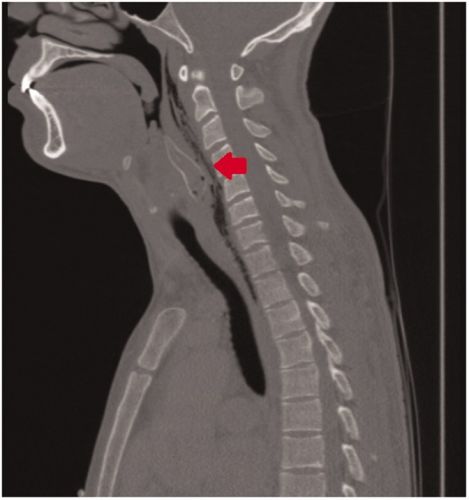

Спустя пару часов, когда все кустарные методы были испробованы, друзья отвезли шутника в ближайшую клинику. Странный пациент не захотел объяснить врачам, в чем причина его бедственного положения и просто жаловался на то, что подавился пищей. Но рентген сразу же показал, что внутри парня находится рыбка и пришлось признаться в исполнении дурацкого трюка.Врачам удалось извлечь мертвую рыбку из горла пациента, после чего ему был назначен недельный курс антибиотиков. Парень отправился домой, а останки бедного сомика — в музей естественной истории города Роттердам, где их могут увидеть все желающие.